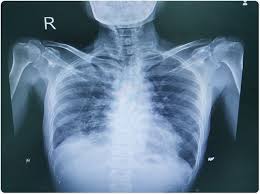

Interstitial lung disease radiology. On a Chest X-Ray it can be very difficult to determine whether there is interstitial lung disease and what kind of. Leflunomide-induced acute interstitial pneumonia. IIPs include seven entities.

Interstitial lung disease results in six distinct radiologic patterns of abnormality. Interstitial lung disease ILD drug-induced interstitial lung disease. We describe demographic radiologic histopathologic and molecular features and p16 expression in patients with telomeres 10th percentile shortened telomeres and compare them to patients with telomere length 10th percentile.

Morphologic classifications of lung conditions diffuse interstitial lung diseases in particular have been undertaken both at the microscopic pathologic patterns and gross radiographic or thin-section computed tomographic CT patterns level. Reticular nodular high and low attenuation table. The lung interstitium is the space where the air sacs called alveoli come in contact with connective tissue and blood vessels to exchange oxygen and carbon dioxide.

Radiographic evidence of interstitial fibrosis consisting of a reticular pattern that involves mainly the lower lung zones is seen in only about 3 of patients who have systemic lupus erythematosus. Interstitial lung disease ILD in pediatric patients is different from that in adults with a vast array of pathologic conditions unique to childhood varied modes of presentation and a different range of radiologic appearances. By contrast interstitial abnormalities are seen in approximately 30 of patients at high-resolution CT 21 22.

In ILDs scarring damages tissues in or around the lungs air sacs and airways. On HRCT there are four patterns.